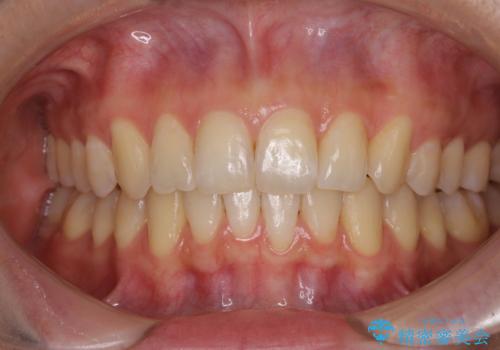

カリエールディスタライザーを併用したことで、確実かつ短期間で治療を終えることができました。

- 1年6ヶ月

- 10-30回